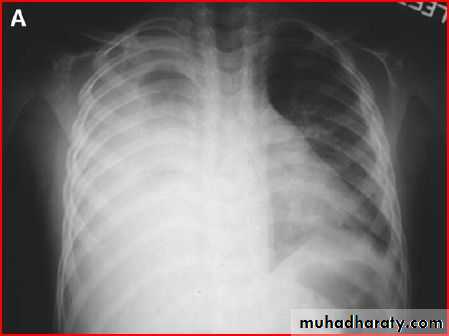

Diaphragmatic hernia

Rt. Diaphragmatic hernia or diaphragmatic eventration

Rx >> endotracheal tube and o2 and NG tubeDiaphramatic hernea and endotracheal tube

Rt. Diaphragmatic hernia (rare) + pneumothorax in lt. due to lung hypoplasia